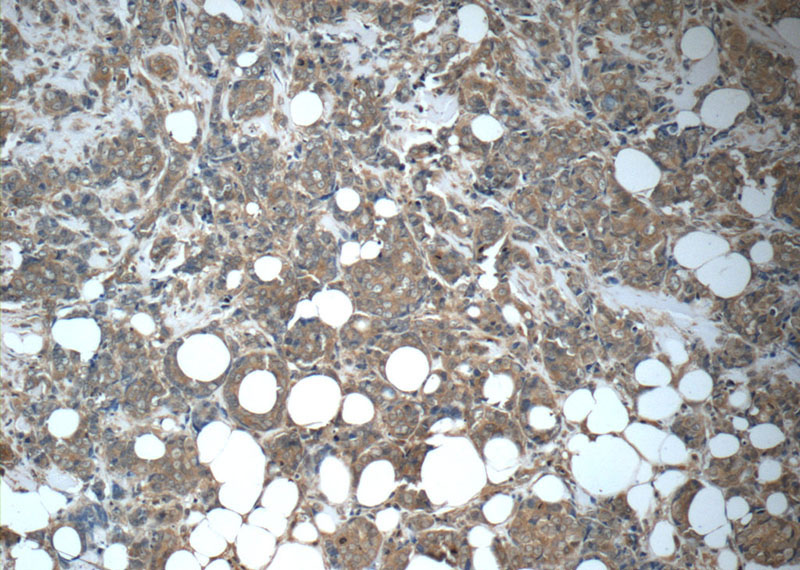

FGFR1 Mouse Monoclonal Antibody

FGFR1 Antibody 60325 1 Ig Proteintech